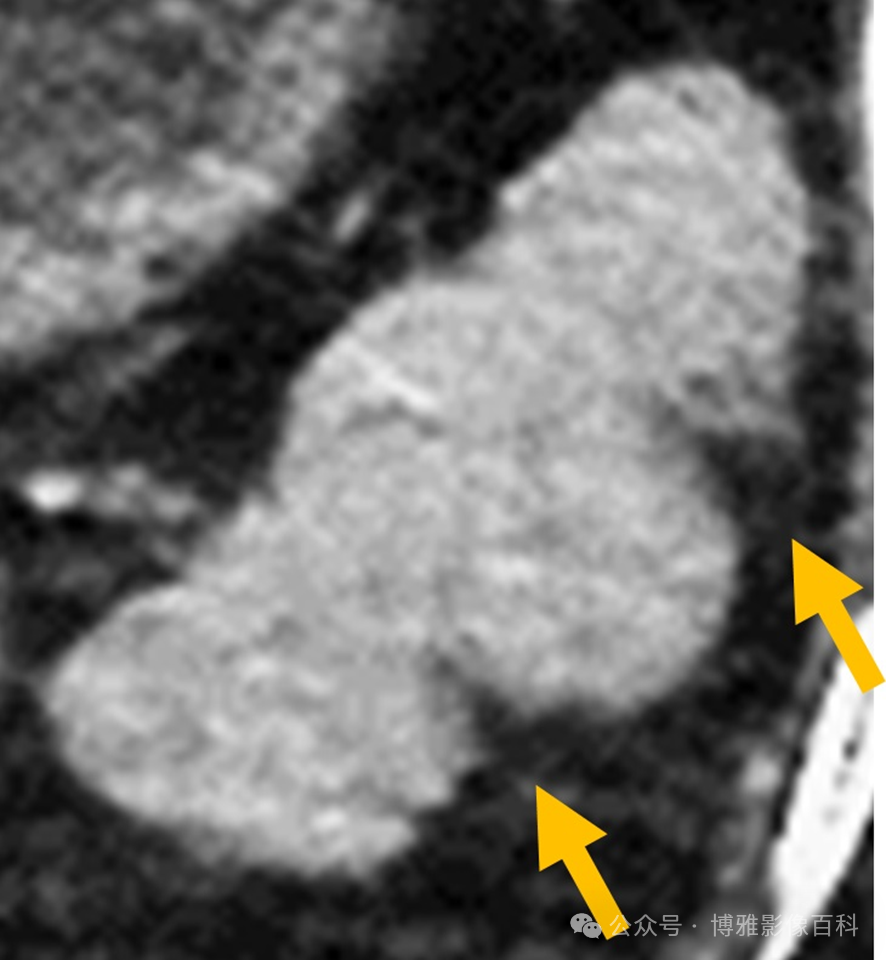

脾缺血:原因:栓塞、血液疾病、休克、门静脉高压、胰腺炎、外伤、医源性(介入手术、手术)

影像表现:梗塞的外观取决于闭塞的位置,无论是由于栓塞或异常细胞(血液学过程):脾动脉实质内分支:楔形低密度,顶点位于远端梗阻处,基底部朝向脾包膜。

3beac00f451eea73897133446db643ab.png

图12:CT门静脉期。楔形脾梗死脾动脉:普遍性实质密度减退或不增强,脾增大(由于水肿)

图13:CT门静脉期。脾弥漫性梗死与肝梗死一样,其轮廓边缘是由梗死的时间顺序决定的。在某些梗塞中,由于侧支循环(胃短动脉),亚急性期可能出现“皮质边缘征”。